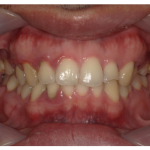

虫歯治療の前にセルフケアの指導とクリーニング・SRPを行い歯周病を改善した症例

治療前 治療後 相談内容 「左上グラグラして昨晩から ...